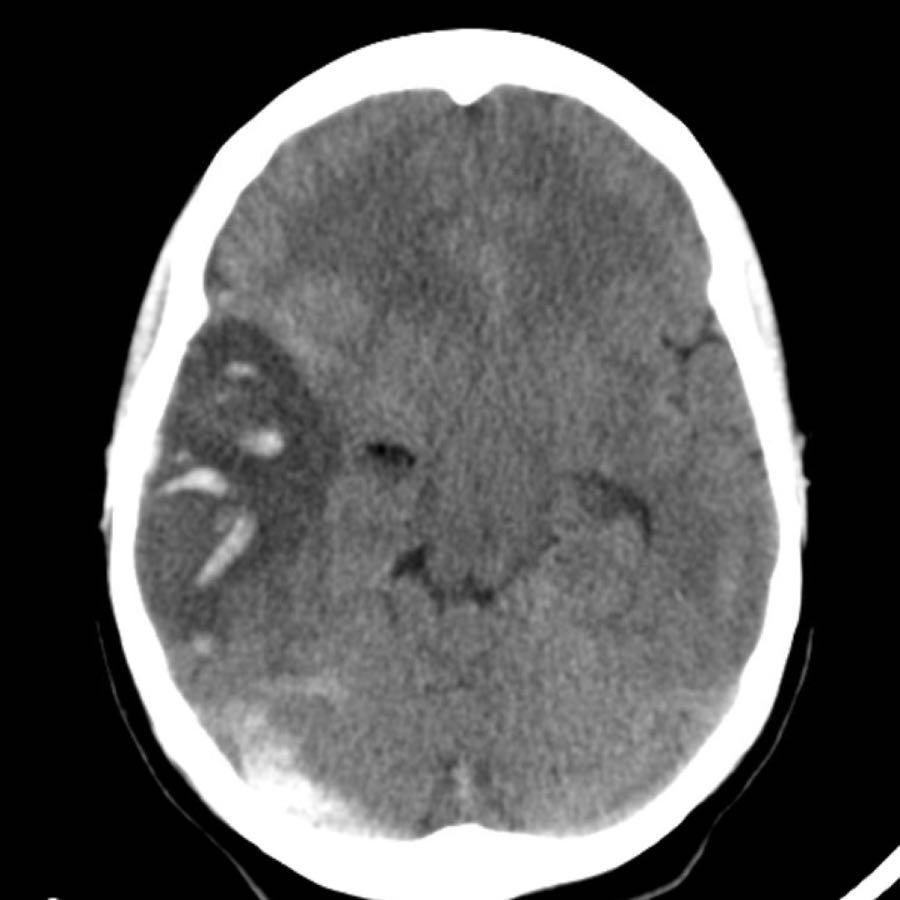

Dưới đây là một số ví dụ về xuất huyết thùy não.

Chảy máu vào hệ thống não thất trong xuất huyết thùy não ít phổ biến hơn so với xuất huyết do tăng huyết áp do vị trí ngoại vi hơn.

Chỉ khi tổn thương rất lớn mới có thể gây chảy máu vào hệ thống não thất (hình).

Bệnh nhân này tử vong vào ngày hôm sau.

Không có chẩn đoán xác định nào được đưa ra, nhưng được cho là trường hợp CAA.